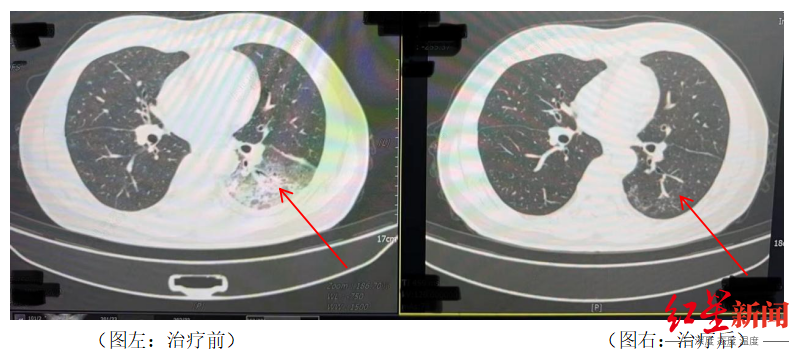

近日,全国多地气温逐步升高,不少人选择开空调纳凉。然而,四川成都市民李先生在开启尘封一年的空调后,竟意外患上了严重的肺炎,左肺“白”了近一半,这是怎么回事?